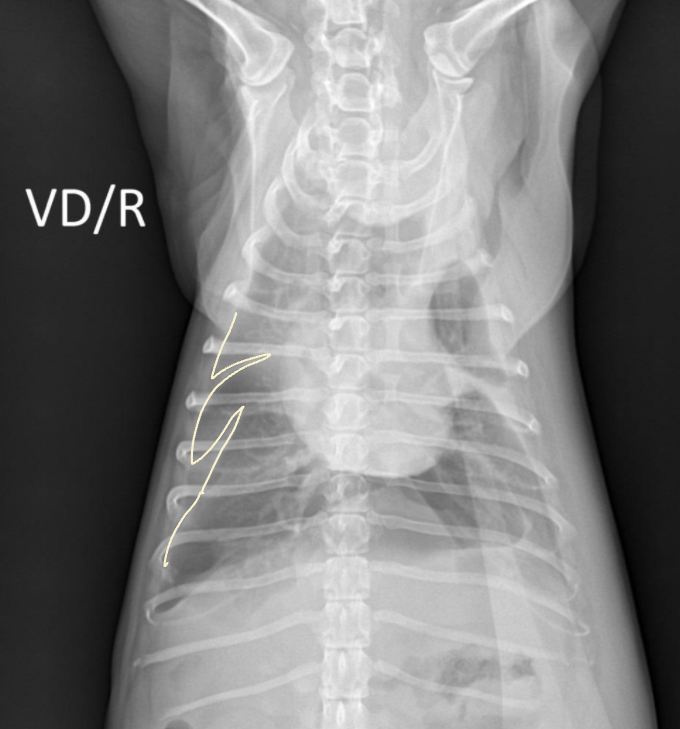

• 우 4엽, 좌 2엽으로 총 6엽이다.

• 외측상은 겹쳐 보여 선호되지 않고, DV나 VD - 특히 VD가 선호된다.

• DV : 안정된 자세, 기흉 촬영

• VD : 흉수 촬영

• 호흡곤란, 기흉 의심될 때는 DV 촬영 (자세 뒤집으면 힘들어함)